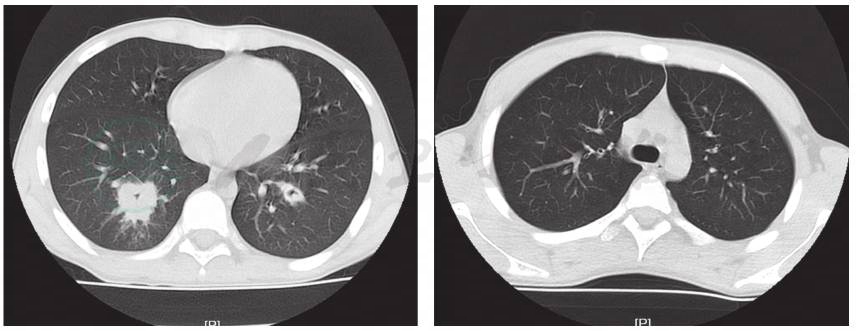

辅助检查:血常规:白细胞计数10.3×109/L,中性粒细胞百分比84.2%,淋巴细胞百分比8.3%,红细胞计数4.36×1012/L,血红蛋白126g/L,血小板 150×1012/L;CRP 87.2mg/L;降钙素原7.22ng/ml;DIC基本正常;肝功能正常;痰培养未见细菌真菌生长;血培养未见细菌生长;6天前肺CT显示双肺多发渗出,以右肺下叶为主伴有实变,双侧胸腔积液(图1);入院前1天肺CT显示双肺下叶实变范围较前增大。双侧胸腔、右侧叶间积液较前减少(图2)。

图1 入院前6天肺CT